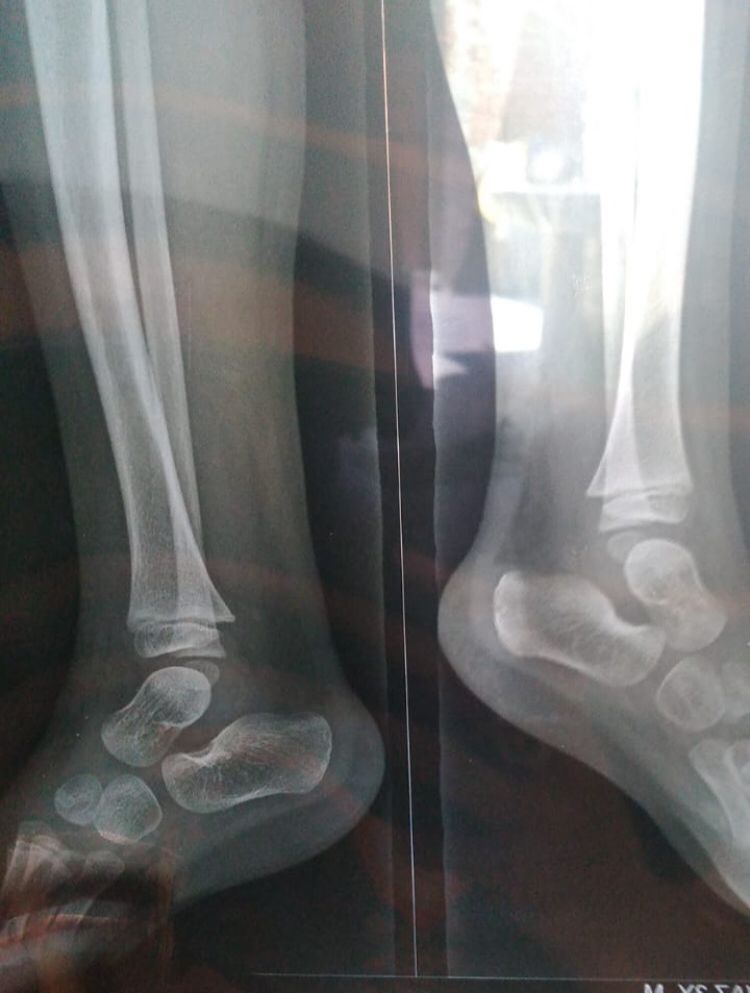

Please have a look at his x-ray

4 years ago

Please have look his x-ray

x-ray